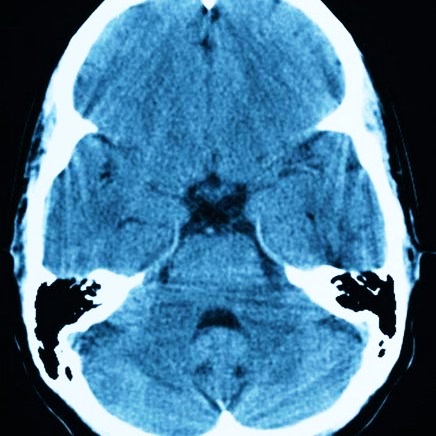

Размеры кистозных полостей определяются разновидностью нозологии – рацемозный, солитарный. Небольшие размеры одиночных очагов (до 6 см) характерны для последней стадии заболевания.

image

Киста на компьютерной томограмме

Рацемозная форма сопровождается образованием множества гроздевидных пузырей внутри церебральной структуры. Полости имеют соединительнотканную капсулу. Вокруг образований находится соединительнотканная оболочка.